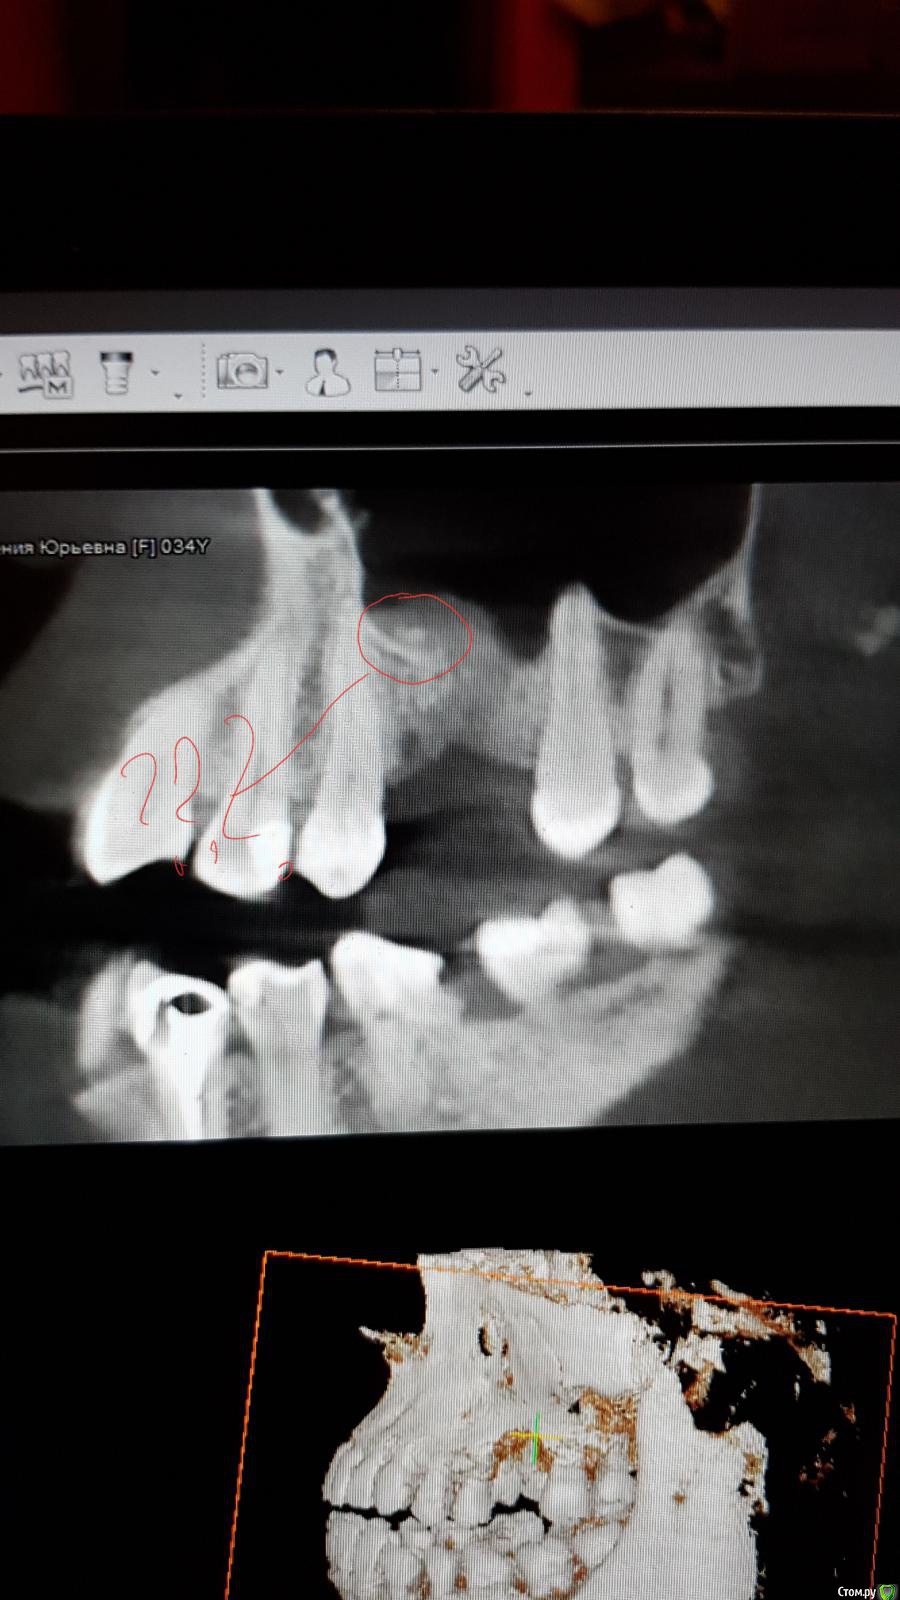

red_butler Опубликовано 14 августа, 2018 Поделиться Опубликовано 14 августа, 2018 в пазухе какая то кака, похоже на силер, это может поддерживать отек 2 Ссылка на комментарий

колесников Опубликовано 14 августа, 2018 Поделиться Опубликовано 14 августа, 2018 Сообщение было? Похоже на фрагмент лунки,дна,графт. За 4мес лунка не оссифицировалась,продолжаются резорбтивные процессы. Чтобы не гадать что будет,расскажите что было. Травматичное удаление? С сообщением? В лунке графт оставляли? Какой? Как закрывали? Как заживало? 2 Ссылка на комментарий

Bier Опубликовано 14 августа, 2018 Поделиться Опубликовано 14 августа, 2018 скорее всего в 1 этап, не вижу особых проблем в пазухе, кроме не заросшей кости в области лунки 2 Ссылка на комментарий